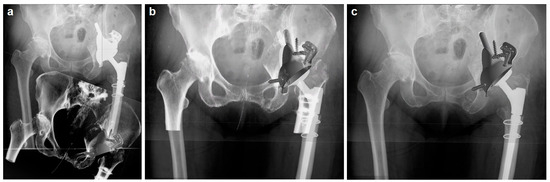

2.3. Custom-Made Acetabular Implants: Planning and Manufacturing

2.4. Surgical Procedure